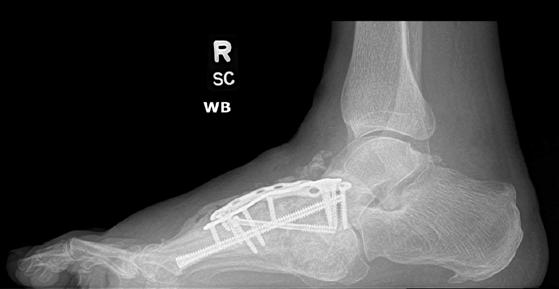

To illustrate the pitfalls of CN treatment, we have presented a 61-year-old male who already underwent midfoot fusion for prior Charcot event (Figure 2). He comes in for a second opinion and declined an ankle fusion and wanted to preserve his motion so that he could drive. The second set of radiographs demonstrate attempted hindfoot fusion that resulted in collapse to the talus bone in the ankle joint (Figure 3). Recent podiatric research shows an alternative treatment option to the traditional rigid fixation. The Charcot flipper foot construct involves fusing the hindfoot while leaving the midfoot mobile to allow for motion to lower risk of further breakdown (2). The final surgery was performed to replacing the dislocated talus with a cadaver bone and fusing the hindfoot with an intramedullary nail all through small incisions for preparation and hardware fixation. The

Figure 3. Result after attempted hindfoot fusion to preserve the ankle motion. The talus collapsed and the foot dislocated medially (third Charcot event). The deformity was so severe that the lateral ankle developed a large wound due to breakdown against the walking boot.